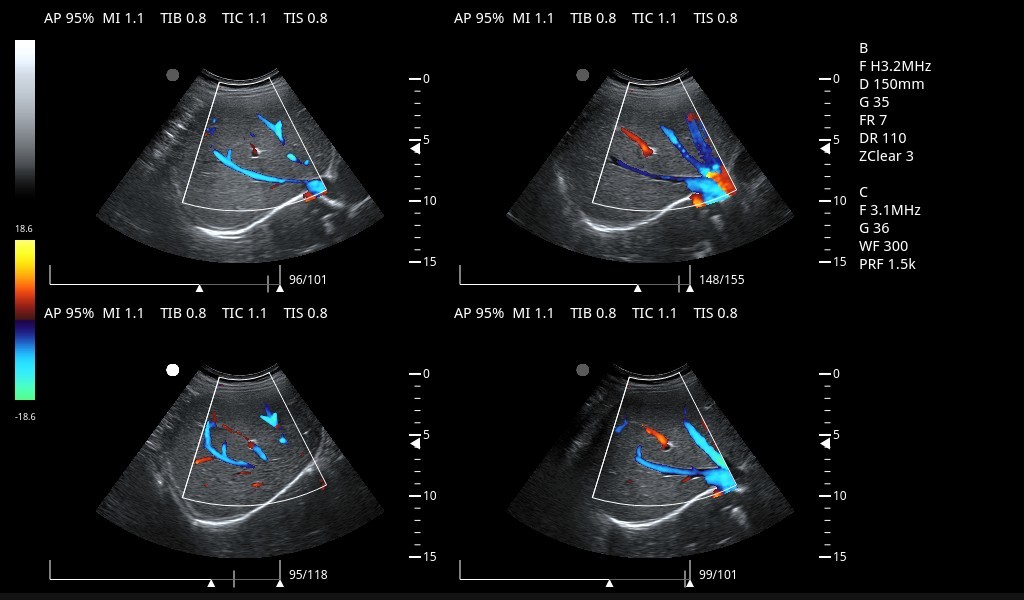

彩色多普勒超声系统

腹部、妇科、产科、心脏、小器官、乳腺、矫形外科、泌尿、血管、肌骨、神经、介入等

空间复合成像、频率复合成像、彩色宽景成像、梯形扩展成像、自适应斑点噪声抑制、反向脉冲谐波成像、血管内中膜自动测量、BCD联动成像、3D/4D成像